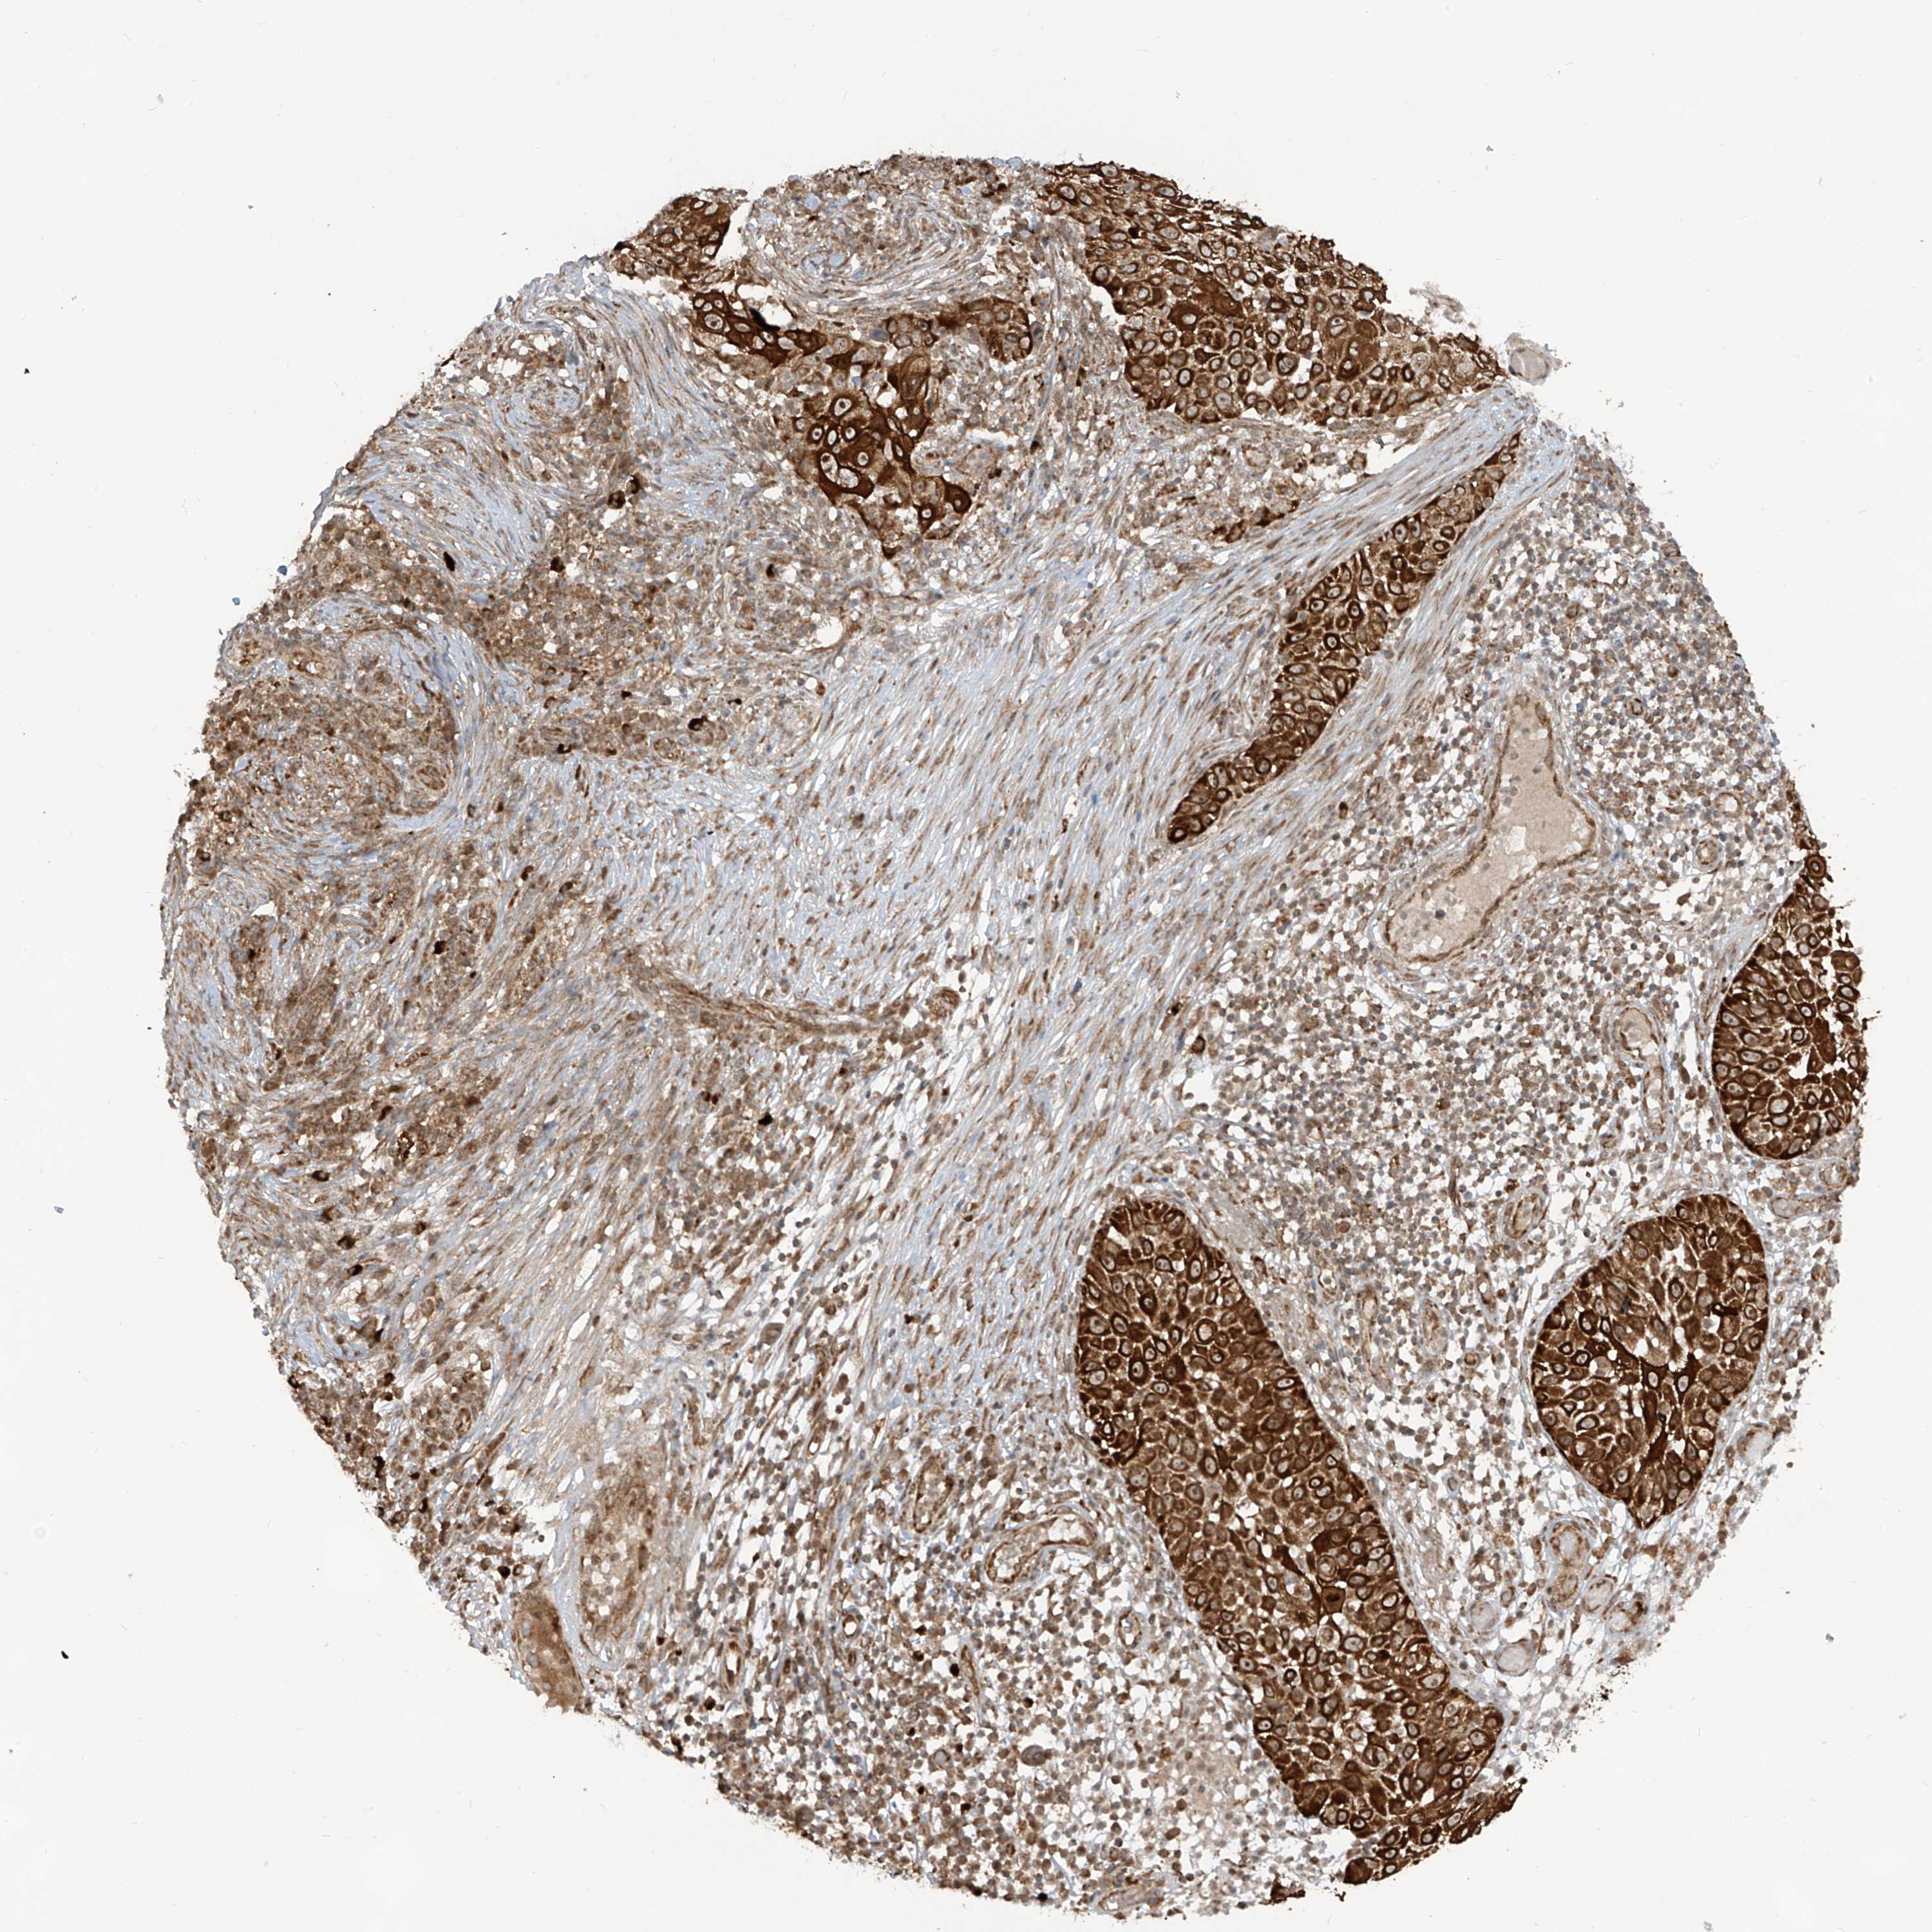

SKIN CANCER - Protein expressioni

A mouse-over function shows sample information and annotation data. Click on an image to view it in a full screen mode. Samples can be filtered based on level of antibody staining by selecting one or several of the following categories: high, medium, low and not detected. The assay and annotation is described here.

Antibody stainingi

Antibody staining in the annotated cell types in the current human tissue is reported as not detected, low, medium, or high, based on conventional immunohistochemistry profiling in selected tissues. This score is based on the combination of the staining intensity and fraction of stained cells.

Each image is clickable and will lead to virtual microscopy that enables deeper exploration of all samples and also displays staining intensity scores, fraction scores and subcellular localization as well as patient and tissue information for each sample.

Antibody HPA034776

Staining

High

Medium

Low

Not detected

Intensity

Strong

Moderate

Weak

Negative

Quantity

>75%

75%-25%

<25%

None

Location

Nuclear

Cytoplasmic/membranous

Cytoplasmic/membranous,nuclear

Basal cell carcinoma

Squamous cell carcinoma, NOS

Squamous cell carcinoma, metastatic, NOS